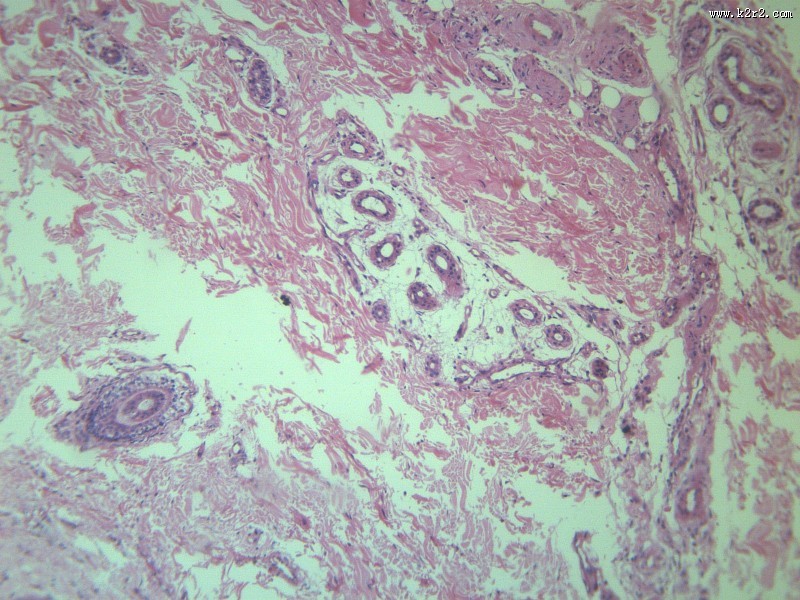

乳头状瘤 - 第11张

乳头状瘤

图集中 / 共有 12 张图片

医学

显微切片

肿瘤

papilloma of papilla